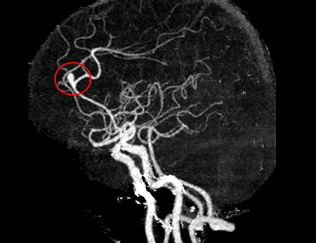

뇌혈관 조영술은 대퇴동맥을 통해 카테터라는 2mm 내외의 관을 삽입한 후 조영제를 주입하고 X-ray를 촬영하여 뇌혈관의 상태를 파악하는 검사입니다. 이 검사는 뇌동맥류, 뇌혈관 협착, 뇌동정맥 기형 등의 진단에 매우 정확하며, 치료 계획을 세우는 데 필수적입니다.

뇌동맥류를 정확하게 진단하기 위해서는 뇌혈관의 상태를 상세히 확인할 수 있는 검사가 필요합니다. 그 중 하나가 뇌혈관 조영술입니다.